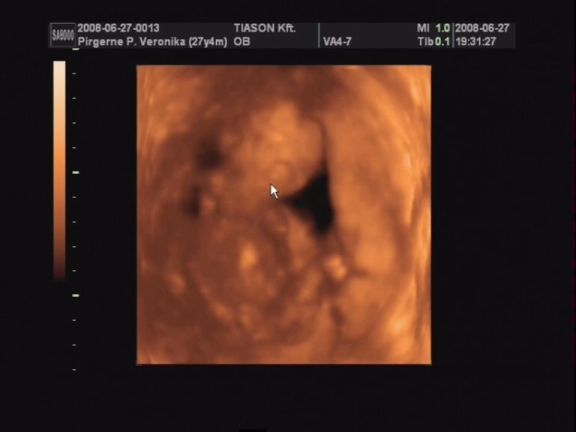

Csodálatos élmény volt az uh!

Nem lehetett még látni, kisfiú vagy kislány van odabent, de nagyon nagyon jó lett a videó. Rengeteget mozgott, rugdalózott, kitámasztotta magát, kalimpált a kezével, iszonyú jó volt. Még a pofijáról is van kép, az is egészen jól látszik.

Egyszóval nagy a boldogságunk, gondolhatjátok. :lol:

Próbálok majd egy két képet levarázsolni a videóról és felrakni hétvégén.